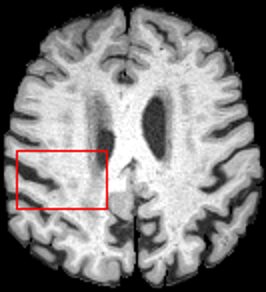

To test the impact of the iterative refinement on YODA’s translation quality, we compared regression and diffusion sampling on the RS data and present additional generation examples in Fig. 6. We observe that diffusion sampling visually resembles the appearance of the acquired images. Regression sampling preserves key anatomical features – the GM/WM boundary, WMHs (Fig. 4), the outline of the pallidum (Fig. 6) – but omits many high-frequency features. To investigate whether iterative refinement during diffusion sampling adds relevant and systematic medical information or only imitates acquisition noise, we performed ExpA sampling, i.e. averaging the output of several ( or ) diffusion trajectories. We observed a gradual loss of high-frequency details when increasing the (see also the supplementary video), indicating that the effect of the iterative refinement is non-systematic. For , the images are visually almost indistinguishable from the initial regression solution (see the supplementary video, and Fig.4 and 6). We directly compared the synthesis results of ExpA () and regression sampling quantitatively and found the differences to be minimal (SSIM: 99.73%, PSNR: 45.30 dB), i.e. diffusion sampling approaches the initial regression solution for a high . The quantitative analysis of the image quality (Tab. 1) showed that diffusion sampling impairs the assessed SSIM and PSNR in comparison to regression sampling for both the in- and external test sets, which we attribute to noise generation (Sec. 3.1). In turn, ExpA averages improved both metrics and, for , performed mostly on par with the regression solution in both test sets in terms of SSIM, while the PSNR in the RS was slightly increased (Tab. 1). However, we observed that ExpA sampling YODA improves the replication of systematic 3D low-frequency image intensity drifts (bias fields) due to the 3D synchronization in 2.5D diffusion sampling. Yet, this apparent advantage did not generalize to the external MBB dataset, as bias fields are MR protocol-specific.

We evaluated the impact of the proposed sampling methods on the performance of the independent, externally trained SHIVA-WMH tool as compared to manual reference labels (Tab. 1). Smoother images (higher or from regression sampling) yielded improved performance over those from diffusion sampling.

To assess the suitability of YODA-generated images for WMH detection independent of segmentation tools, we also calculated the CNR (15) of WMHs. This confirmed that the contrast of WMHs is preserved in the regression images, whereas we noted slightly reduced WMH contrast for diffusion and ExpA-sampled images (Tab. 1).

For BraTS and IXI datasets, we noted the same convergence of visual appearance for diffusion to regression sampling when increasing the (Fig. 4) as observed in the RS. Also, we observed similar tendencies in terms of SSIM and PSNR, and for the performance of the respective downstream tasks (Tab. 2).